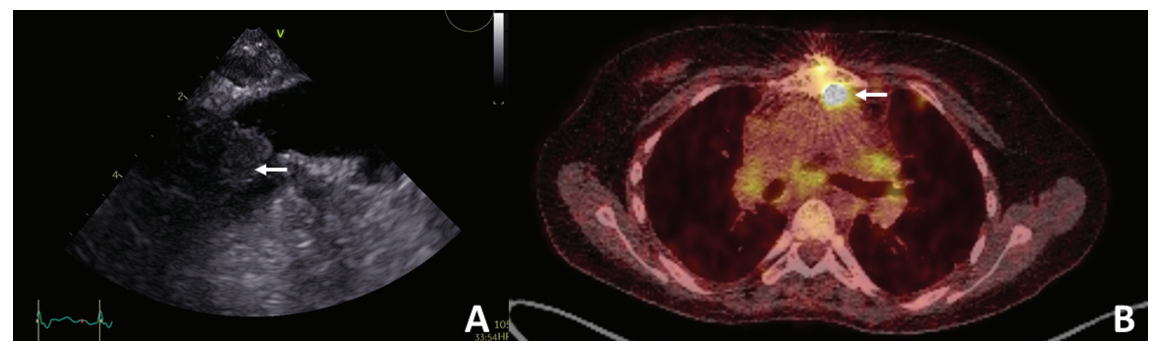

患者入院时发热高达39°C、呕吐,间歇性咳嗽。曾在外院行4次心脏手术及多次导管介入治疗。这些包括法洛四联症矫正术,右心室流出道(RVOT)导管重复扩张,因严重肺功能不全在RVOT植入 Contegra移植物,因Contegra心内膜炎(金黄色葡萄球菌)植入肺部同种移植物,念珠菌引起的胸骨伤口感染,真空辅助封闭(VAC)治疗以及胸骨重新连接与无泵心包缺损封闭过程中的同种移植损伤。术前经食管超声心动图显示,靠近肺动脉分叉处低密度结构(横径约 14mm),符合血栓或赘生物(图1A),引起梗阻(Vmax> 4m/s)。正电子发射断层扫描/计算机断层扫描(PET-CT)显示同种移植物区域的病理示踪剂摄取(图1B)。

图1. (A)经食管超声心动图显示肺动脉分叉附近低密度结构,横径约 14mm,符合血栓或赘生物(箭头)。(B)氟脱氧葡萄糖正电子发射断层扫描/计算机断层扫描(FDG-PET-CT)显示附着胸骨的右心室流出道(RVOT)高活性(箭头)。